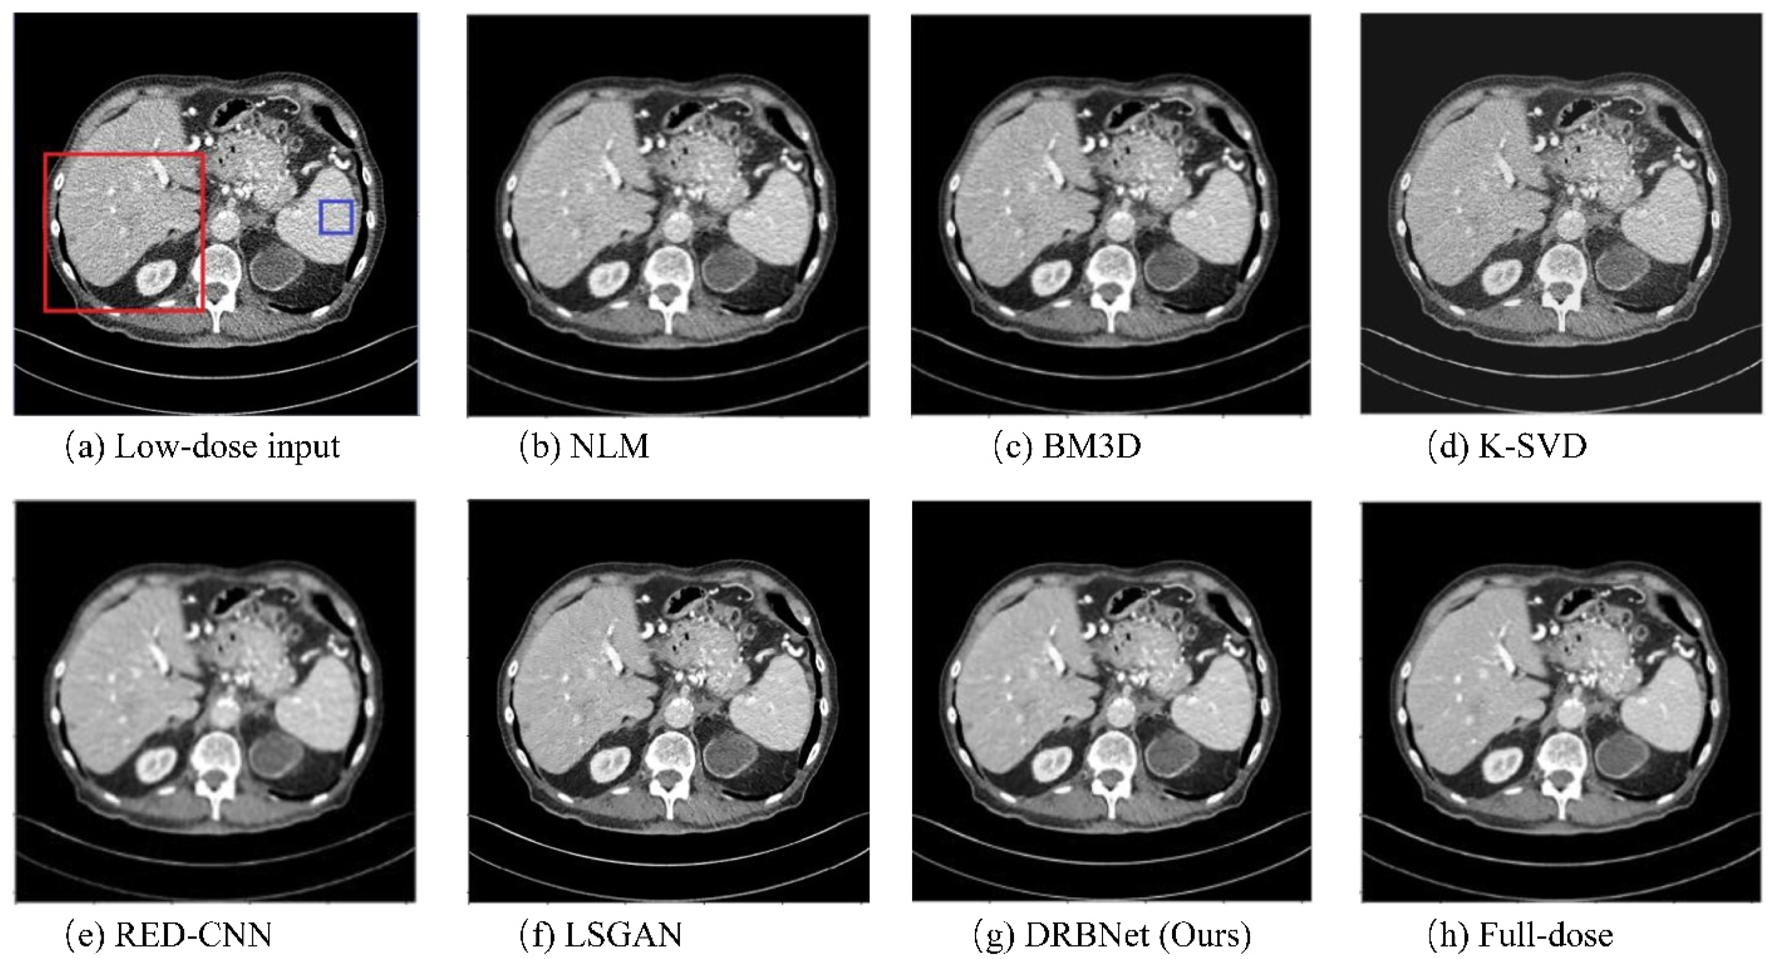

To evaluate the noise reduction performance of our proposed plug-and-play prior for LDCT image denoising, two denoised results of the representative LDCT images are analyzed.

Figures 4–7 show results from proposed DRBNet prior and the compared denoising methods. Figures 4, 5 show the entire CT scans, while Figures 6, 7 focus on the regions of interest (ROIs), marked by red rectangles in Figures 4, 5. The display window for all figures is set to the range of [-160, 240] HU. CT images inherently contain rich textures representing organ and tissue structures. However, as depicted in the figures, the LDCT images are heavily contaminated with noise and artifacts, which can hinder clinicians’ ability to accurately assess lesions, diseases, or tissue morphology. All compared denoising algorithms succeed to some degree in removing noise and artifacts. However, NLM and BM3D provide minimal improvement in noise removal, with noticeable residual noise and artifacts still evident in the enlarged ROI images (see Figure 6b c; Figure 7b,c). The denoising effect of K-SVD is marginally better than that of NLM and BM3D. The results from RED-CNN suffer from over-smoothing, resulting in the loss of fine texture details in the tissue and anatomical structures due to its use of the mean squared error (MSE) loss during training. The denoised CT image from LSGAN reduces noise while maintaining texture information. However, the results obtained using our proposed DRBNet prior, as shown in Figure 4g; Figure 7g, effectively remove noise and suppress artifacts while preserving crucial texture details that are vital for clinical diagnosis.

Figure 4. Results of a low-dose CT scan produced by compared algorithms from the testing set. (a) Low-dose, (b) NLM, (c) BM3D, (d) K-SVD, (e) RED-CNN (f) LSGAN, (g) DRBNet (Ours), (h) Full-dose. The display window ranges: 160 to 240 HU.

In Figure 6, the zoomed-in ROI, marked in Figure 4 with a red rectangle, contains rich tissue texture information. This ROI section includes intricate tissue details that are nearly obscured by significant noise and artifacts. Notably, the textures indicated by the red arrow in Figure 6a are blurred and unclear in the original LDCT input. The NLM, BM3D, and K-SVD methods struggle to restore these fine textures. RED-CNN causes excessive smoothing, resulting in further blurring, while LSGAN still leaves some residual noise that could affect clinical diagnosis. However, in Figure 6g, the result from our proposed DRBNet prior clearly restores the fine texture and removes the noise. In Figure 7g, the low attenuation lesions, highlighted by the red circle and red arrow, along with the subtle details indicated by the blue arrow, are restored by our approach and closely resemble the full-dose target. Overall, the observations from Figures 4–7 demonstrate that the visual results produced by our DRBNet prior are highly promising.